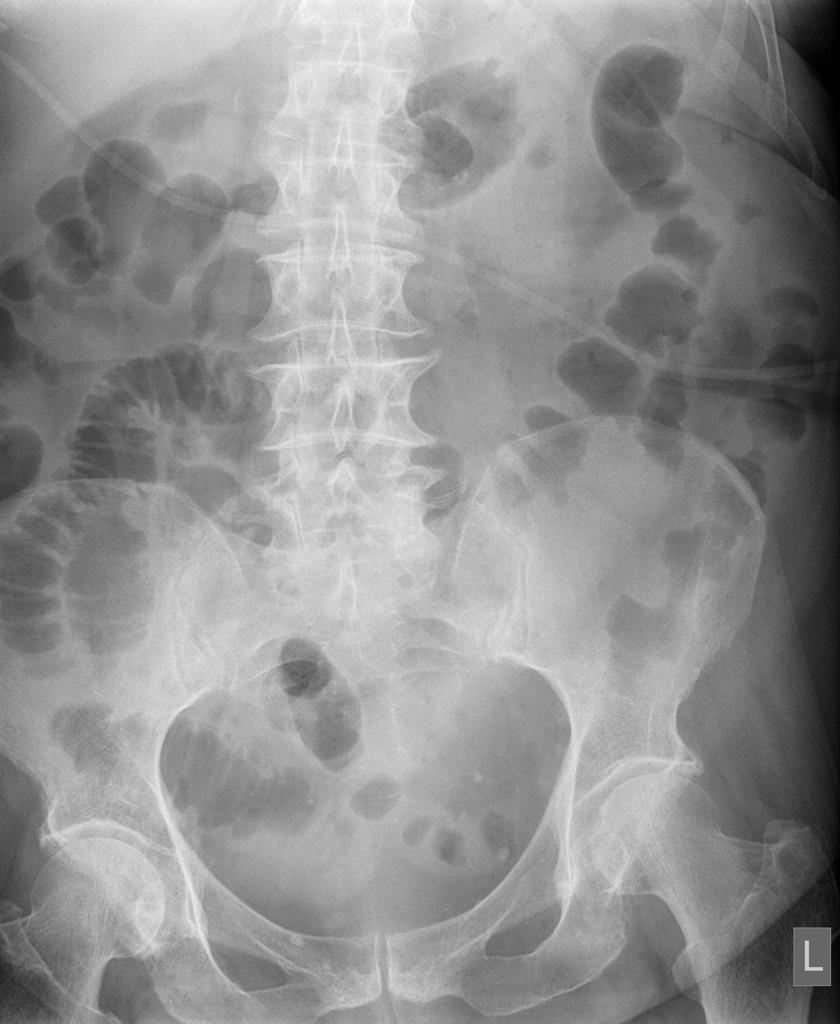

How does small bowel obstruction appear?

>3cm dilation

Dilated loops = coiled spring look

How does volvulus appear?

Sigmoid = coffee bean appearance

Caecal = fetal appearance

What is Rigler’s sign?

Pneumoperitoneum may cause both sides of bowel wall to be visible

What does thumb printing indicate + what is it?

Mucosal thickening of haustra due to IBD

What does a lead pipe colon indicate?

Loss of haustral markings secondary to chronic colitis